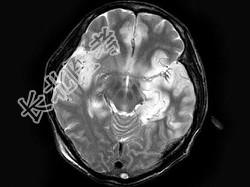

- 单项选择题男,46岁, 头痛、呕吐1周,MRI如图, 最可能的诊断是 ( )

A、脑梗死

B、病毒性脑炎

C、胶质瘤

D、化脓性脑炎

E、未见异常